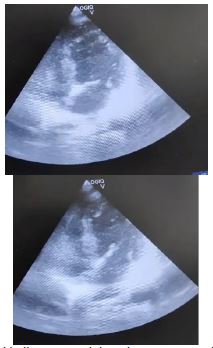

During the preoperative evaluation, the ECG and 2D echocardiogram were normal (Figure 1). However, the patient’s condition later deteriorated with an increased dose of noradrenaline and vasopressor support, and a Point-of-Care Ultrasound (POCUS) examination revealed hypokinesia in both the apical and mid-regions of the heart, along with apical ballooning, indicating left ventricular dysfunction (Figure 2). A cardiologist subsequently confirmed these findings. The blood gas analysis showed metabolic acidosis with a lactate 3 mmol/lt. Further investigations are shown in Table 1.

Figure 2: Arrow depicting apical ballooning and hypokinesia.